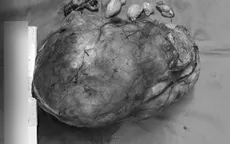

Loại bỏ khối u nặng 5,5kg bao trùm toàn bộ thận trái bệnh nhân VTV.vn - Khoa Phẫu thuật Ống tiêu hóa, Bệnh viện Trung ương Quân đội 108 đã thực hiện thành công ca phẫu thuật cắt khối u "khổng lồ" chèn ép nhiều bộ phận.